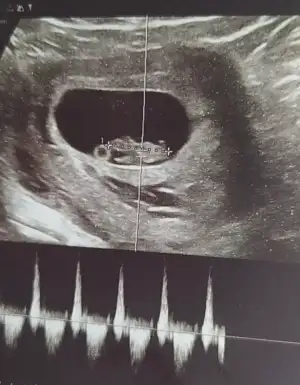

Cinsiyet tahmini alabilirmiyim

Teşekkürler nerden anladınızKız bence

rica ederim kesenin şeklindenTeşekkürler nerden anladınız

Benim attığım ultrason görüntülerine göre yorumlar mısın rica etsemtahmını bence kız :)

Sizce benim nedir 11+1rica ederim kesenin şeklinden

Erkeğe benziyor amaSizce benim nedir 11+1

Canım seninkisinin fetus çok küçük belli olmuyor